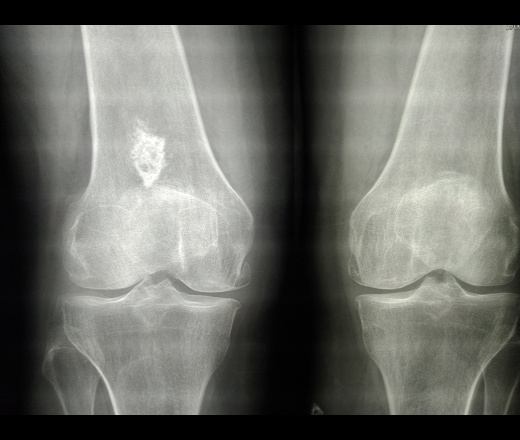

Рентгеновские снимки остеосклероза костной ткани